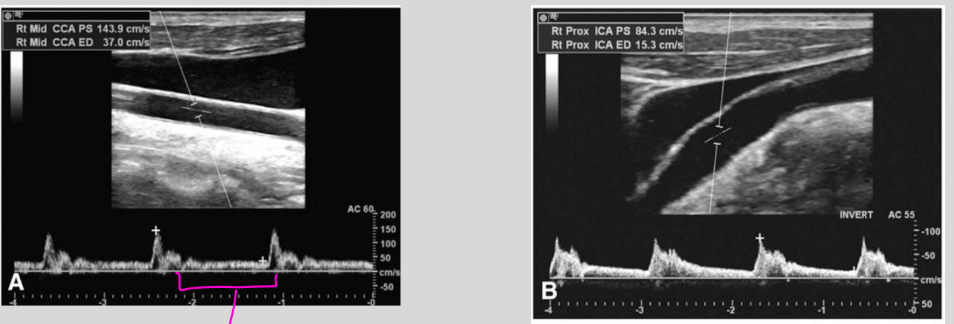

what waveform is this

Aortic Valve Stenosis